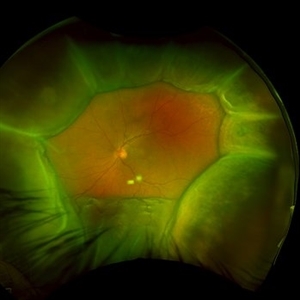

66 year old male presented with a 4 month vision of painless decreased vision in the left eye. Clinical findings consistent with idiopathic uveal effusion syndrome. Fundus autofluorescence imaging shows presence of leopard spotted pigmentation.

Photographer: Dr. Angela Rico, Retina Specialists of Tampa